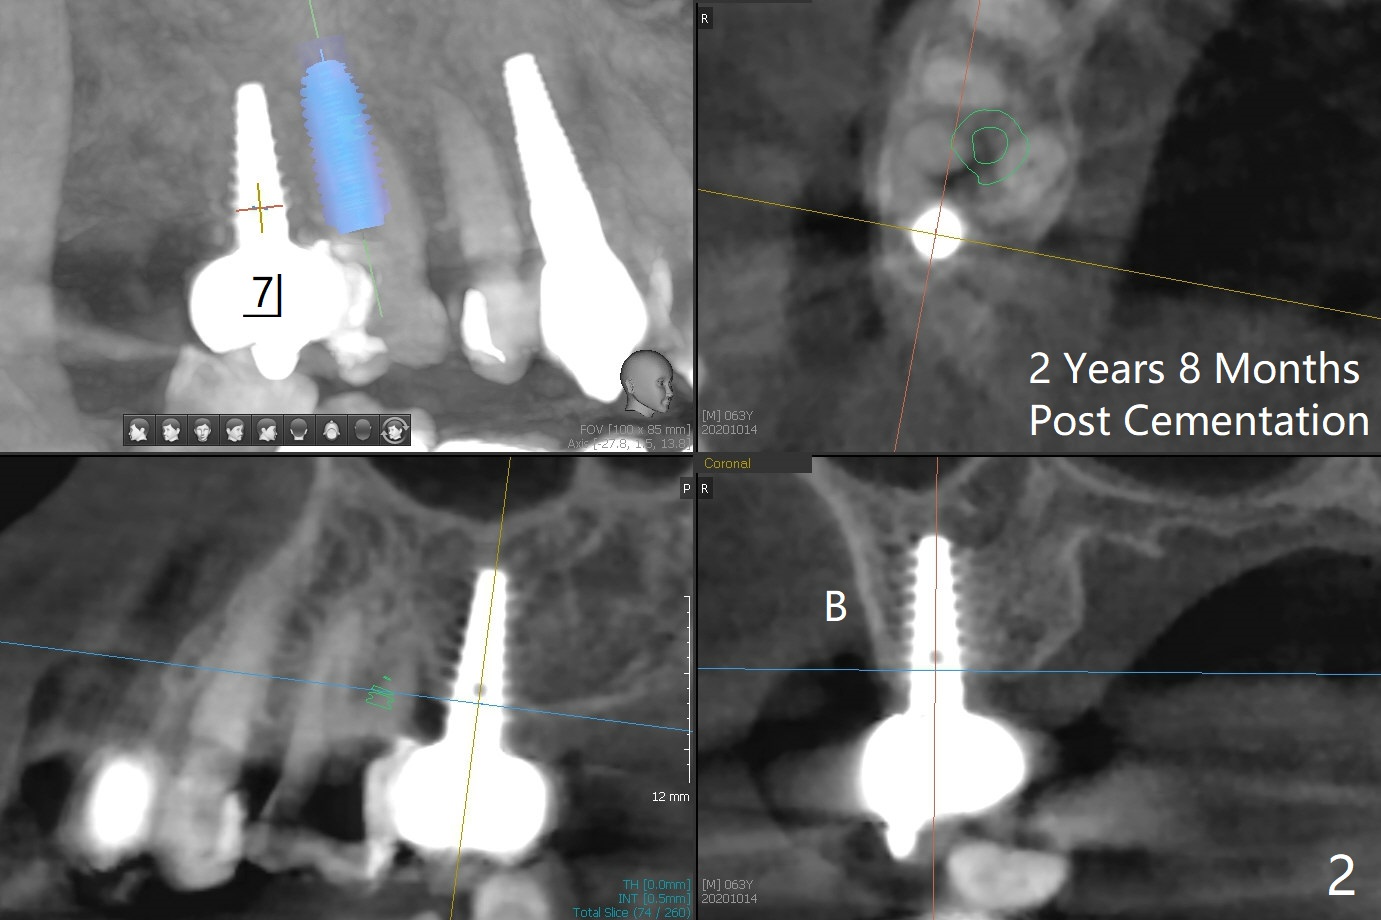

63岁女右上6远中龋齿在邻牙植牙牙冠粘固后2年8个月坏的严重(图一),病人决定拔除种植。之前嘱咐她回来修复,部分由于新冠病毒,她拖延治疗。今后需要建立一个植牙后完整随访和严密检查系统,减少继发龋。分析四个植牙(图二,四至六)表明骨质宽度优越,右上6即刻种植应该没问题(图三)。植体选择与邻近一致。Prevent Molar Periimplantitis (Protocols, Table) No Neighboring Caries Metronidazole Magicore Cases 手术 2 Xin Wei, DDS, PhD, MS 1st edition 10/14/2020, last revision 11/17/2020